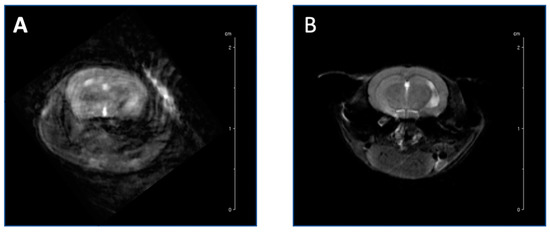

The newly designed mouse holder (Supplemental Figure S1), in comparison to the Stenroos design [17], has an altered neck bridge with a larger inner cutout, and a reduced inner volume of the nose cone that consists of a shaved top surface to enable the surface coil to fit, an indented inner surface, a longer bed for the mouse to lay on, and the incorporation of an oxygen hose through which a tooth bar is placed to reduce head motion [17]. Highly motion-sensitive T2-weighted images, attained through awake-animal imaging, demonstrated the reduction of motion artifacts when using the newly designed restraint and new acclimation procedures (Figure 5A) compared to the original holder (Figure 5B).

Figure 5. Highly motion-sensitive T2-weighted axial images of the brains of two mice show the significant reduction of motion and artifacts during the awake MRI imaging process. Anatomical image acquired with previously designed mouse holder (A) vs our newly designed mouse holder (B).